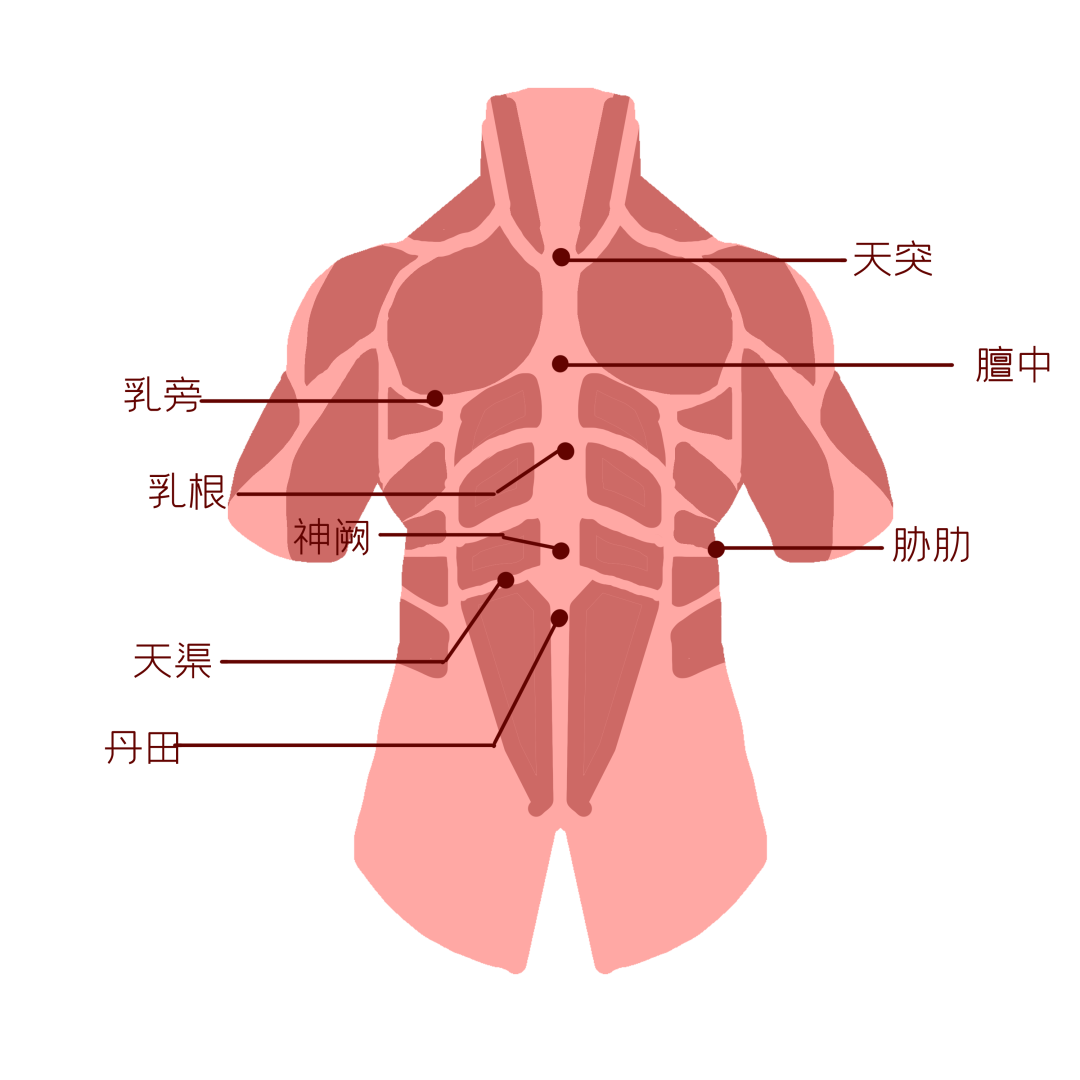

先来说说中医是如何认识乳房的?

对乳房经络、解剖、生理、病理的认识,在最早的中医经典著作《内经》中已有记载,后世医家也多有论述,如“女子乳头属肝,乳房属(脾)胃”。

一般认为,对乳房生理、病理影响最大者为:肝、肾、脾、胃,其功-能是否正常以及肝胃两经,冲任二脉是否通调。若经脉闭阻不畅,冲任失调,则可能导-致多种乳房疾病的发生。